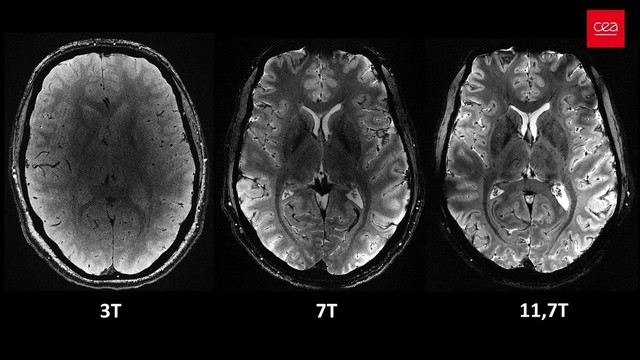

A mágnesesrezonancia-képalkotó berendezések erős mágneses térrel veszik körbe a vizsgált testrészt. Míg a legtöbb kórházi eszköz 1,5-3 tesla (T) erősségű, a mostani gép 11,7 T-vel dolgozik, ami rendkívül részletes felbontást tesz lehetővé sokkal rövidebb idő alatt. Ez különösen fontos, mivel a betegek csak rövid ideig tudnak mozdulatlanul feküdni. Az új technológia nagy segítséget jelenthet az Alzheimer-kór és a Parkinson-kór kutatásában, mivel részletesebb információkat szolgáltathat az agy elváltozásairól, ami hatékonyabb terápiák kifejlesztését teszi lehetővé.

Agyi felvételek